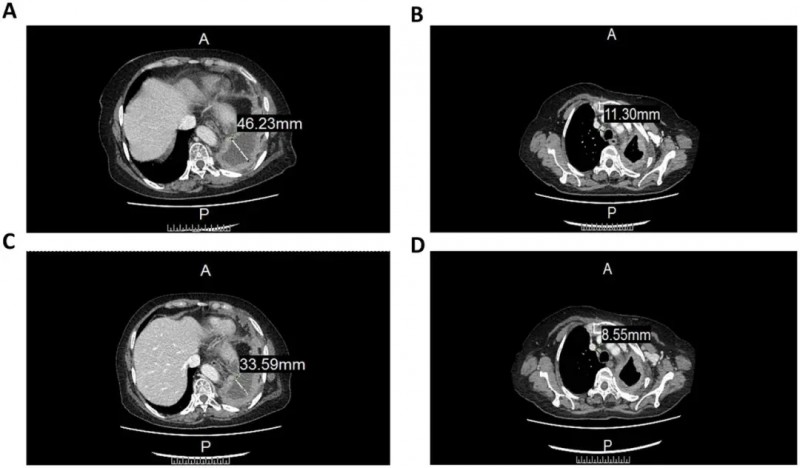

结果显示:CCCR-NK92细胞展现出强大的抗肿瘤活性,肿瘤病灶明显缩小。CT影像数据显示,患者左肺包裹性胸腔积液厚度从46.22mm降至33.59mm(详见下图A/C);前气管-后腔静脉间质区域的淋巴结直径,也由11.3mm缩小至8.55mm(详见下图B/C)。这一案例为晚期肺癌治疗提供了重要临床依据,证实了CCCR-NK92疗法对肿瘤病灶的有效控制能力

▼CCCR-NK92细胞治疗前后CT图像对比